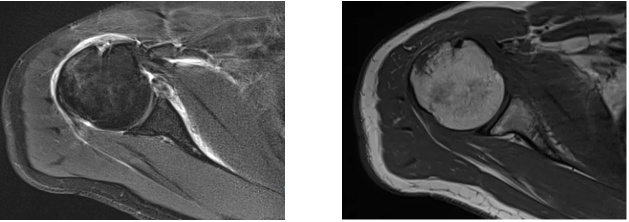

病例1

病史摘要:男性,44歲,跌傷致右肩關(guān)節(jié)疼痛數(shù)天,活動不利。

MR圖示:右側(cè)肱骨后外上方局部骨皮質(zhì)塌陷,并鄰近皮質(zhì)下斑片狀壓脂高信號影(箭頭);前盂唇撕脫,前方見低信號游離骨片影(三角形)。